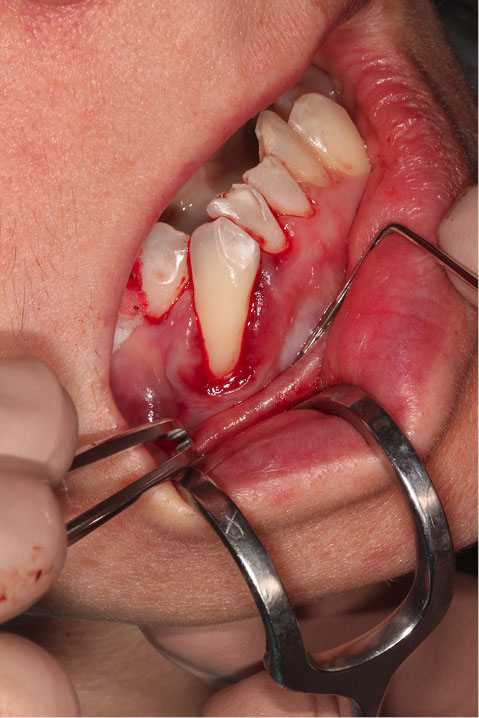

Figure 2 shows the final tunnel preparation before the placement of CTG. Figure 3 shows the harvested CTG positioned on the exposed root surface to check its dimensions before placement inside the tunnel on the buccal aspect of tooth #43. Figure 4 shows suturing after the CTG has been positioned inside the tunnel. Please note that the sutures were kept longer than usual to prevent the poking of the suture ends into the lower lip and buccal mucosa. Figure 5 shows the postoperative condition at five-week interval.

Figure 2. Final tunnel preparation prior to the placement of CTG The harvested CTG positioned on the exposed root surface to check its dimensions prior to placement.

Figure 3. The harvested CTG positioned on the exposed root surface to check its dimensions prior to placement inside the tunnel on the buccal aspect of tooth 43.